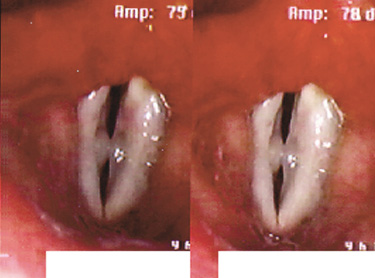

Through the microlaryngeal surgery vocal cyst is removed then PDL laser is being applied to avoid scarring and closing of the

surgical point. It is important to remove the root completely to prevent recurrence.